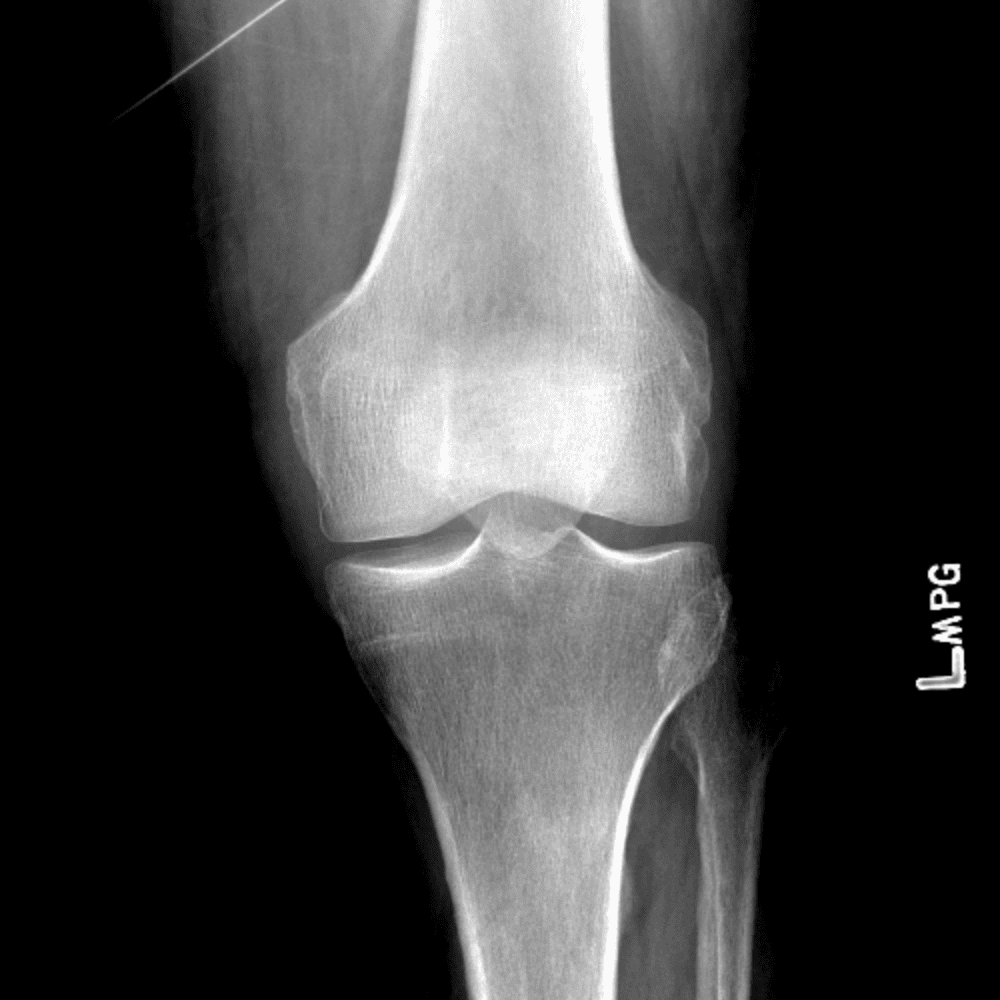

Simula o plantão incluindo casos sutis ou difíceis e alguns normais.